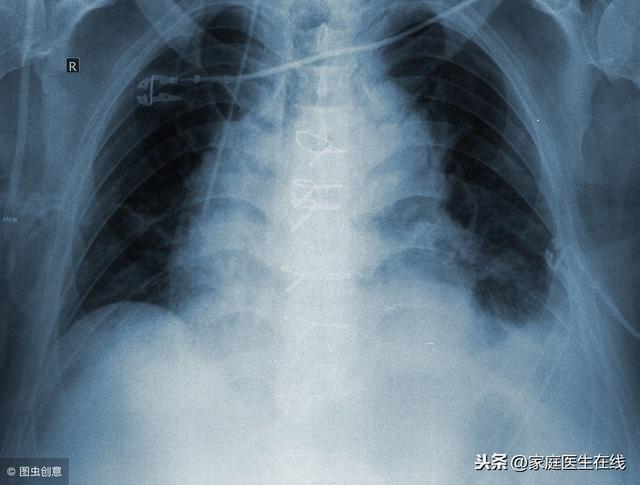

肺炎是春季常见的一种呼吸道疾病 , 一般是发生在婴幼儿身上 , 主要是因为病毒或者细菌所引起的 。 肺炎发病比较急 , 严重情况下是会直接危及到孩子生命健康的 , 因此作为家长一定要将肺炎与感冒区分好 。

当孩子患上肺炎之后会出现喘息、发高烧以及咳嗽等 , 一般上呼吸道感染几天之后就会发病 , 刚开始会出现发高烧或者咳嗽 , 体温会高达39摄氏度 。 若孩子没有发烧 , 但有呛奶以及咳嗽症状 , 几乎不吃奶 , 精神差 , 睡觉时也一直哭闹不止 , 睡眠及其不安稳也应警惕肺炎 。 重症的患者会出现嘴唇周围发青以及鼻翼扇动等呼吸困难的症状 , 甚至会出现心力衰竭或者呼吸衰竭 , 也有一部分患儿会出现腹泻呕吐以及腹胀等 。

大部分小儿肺炎会伴有发高烧的症状 , 并且体温高达38摄氏度左右 , 会持续三天 。 使用退烧药物只能暂时退一会儿 , 如果是因为感冒所引起的发高烧 , 体温一般在38摄氏度以下 , 并且持续的时间短 , 只要使用退烧药物就能退烧 。